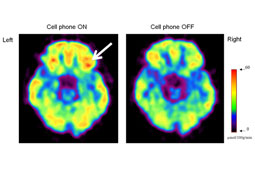

Η ακτινοβολία 4G των κινητών τηλεφώνων επηρεάζει τον εγκέφαλο

03-aktinobolia-9Πρόσφατα το περιοδικό Clinical Neurophysiology δημοσίευσε μελέτη η οποία δείχνει πως μόλις 30 λεπτά έκθεσης στην ακτινοβολία κινητών τηλεφώνων, επηρεάζει την εγκεφαλική δραστηριότητα και στις δυο πλευρές του εγκεφάλου.